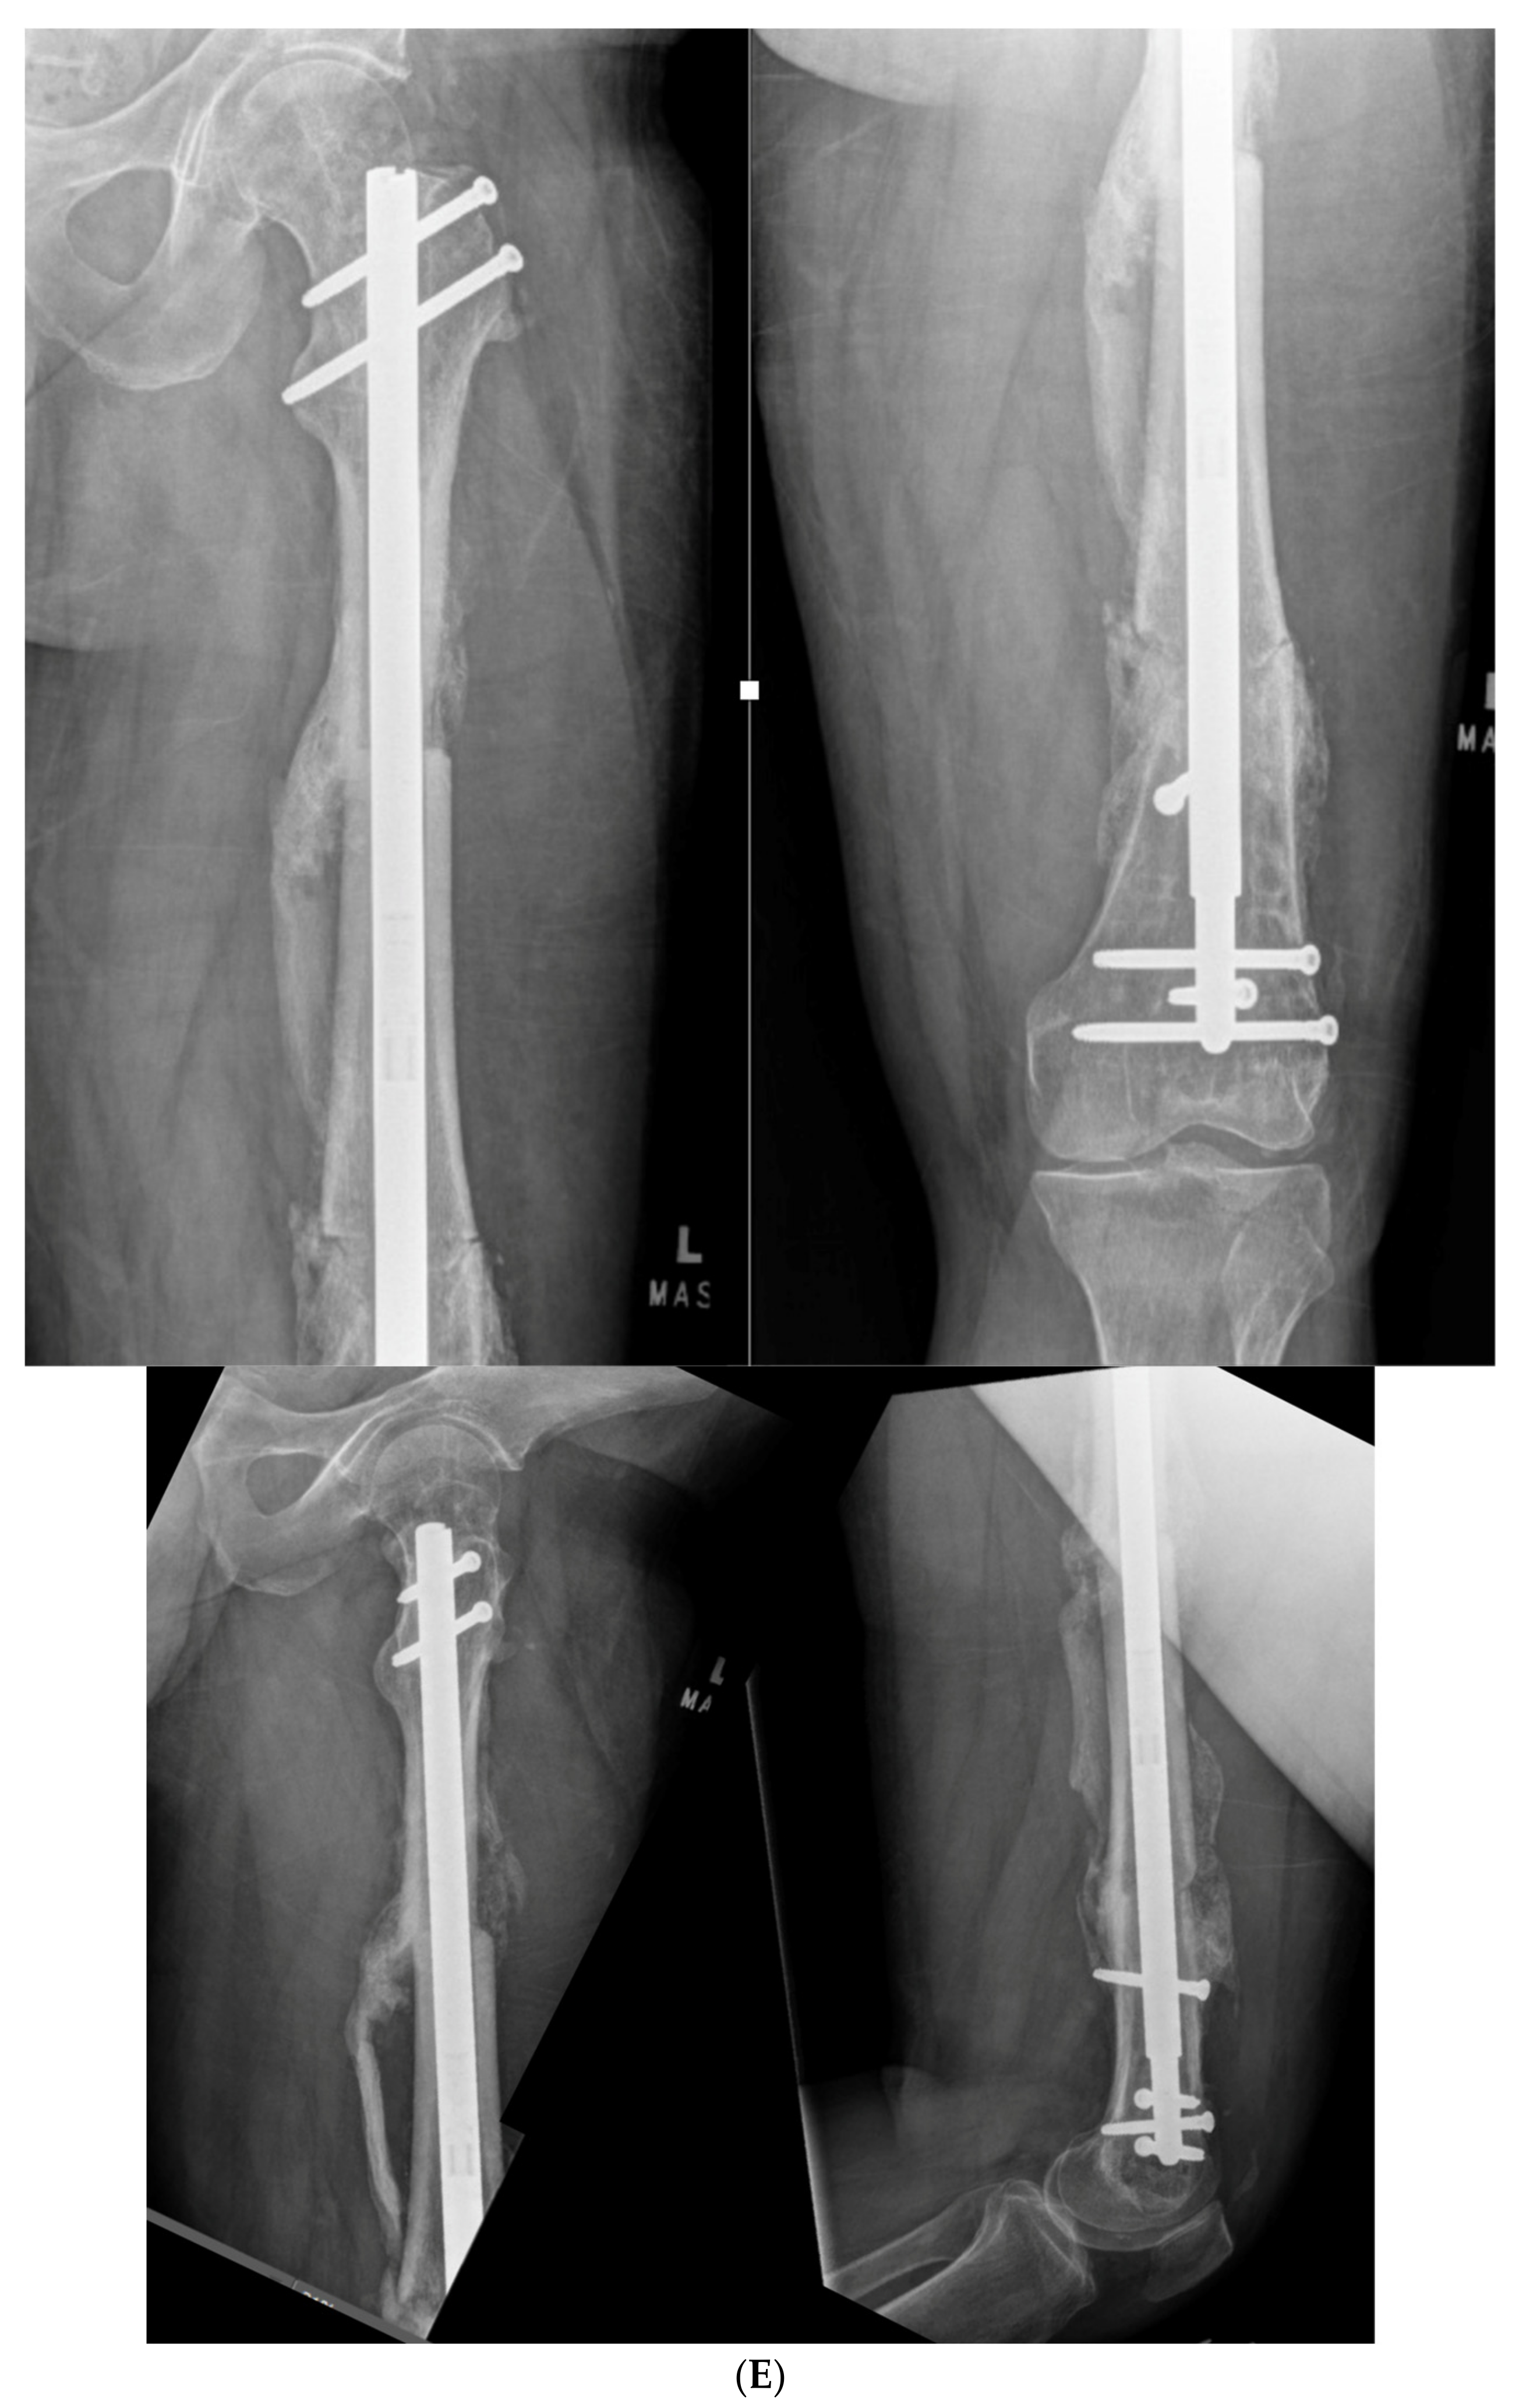

3.1. Case 1-Multifocal Correction with Intramedullary Nail: Femur

The patient is a middle-aged female with no comorbidities other than obesity who presented 26 years after an open diaphyseal femur fracture with more than 10 surgeries for attempted union and eradication of infection. The patient presented with complaints of pain at the mid-femur and knee, a chronically draining sinus of the lateral thigh, and concern for a 2-cm-short left leg. No rotational deformity is found. The limb clinically appears normal in the coronal plane. The patient has a 15-degree knee contracture. X-rays reveal a malunion of the left femur with bone sequestrum and retained hardware (Figure 6A). A metabolic workup, including the vitamin D level, is normal. The CT scan characterizes the pathological bone, allowing for precise localization of the sequestrum (Figure 6B). A deformity analysis reveals a primarily sagittal plane deformity with limb shortening. The traditional CORA analysis demonstrates translation with angulation, as demonstrated by a CORA located outside of the deformity. With the expected multiple stages, a double-level focal dome was chosen over clamshell, allowing stable weight-bearing while not requiring an extended femoral osteotomy to heal through pathological bone. The other consideration for this patient was radical en bloc resection of the diseased bone, with either bone transport or secondary reconstruction with a compressed allograft intercalary segment. This concept was reserved as the option if the current plan failed.

(A) Middle-aged female with 26 years of an infected draining sinus of the left femur with malunion and shortening. The intersection of the two blue lines represents the CORA of the proximal and distal diaphyseal segments (C1). A CORA outside of the deformity reveals translation in addition to angulation. The intersection of the green line with each blue line represents an alternative where the central deformed segment is also incorporated into the analysis, revealing two CORA center points for double-level osteotomy (Ca and Cb). (B) The patient was found to have retained hardware and a bone sequestrum. Sequestrectomy with antibiotic local delivery via a coated intramedullary nail with concomitant systemic antibiotics would promote infection eradication. (C) The patient underwent double-level focal dome osteotomy at the time of initial debridement. The patient had two sequential debridements over 10 days. Stabilization using an interlocking antibiotic coated nail was placed during the final debridement. (D) Five months postoperative, where the distal osteotomy was autogenous-grafted from the patient’s contralateral femur due to the persistent osteotomy gap. Chronic suppression oral antibiotics were recommended; patient voluntarily stopped antibiotics at 24 months. (E) Three-year final follow-up with normal serological markers and no sign of recurrence. Osteotomies healed. Soft tissue healed.

The patient underwent double osteotomy using focal dome osteotomy at Ca and Cb (Figure 6C), with retained hardware removal and resection of the infected sequestrum and surrounding diseased bone. A direct lateral approach to the thigh was used, and the diseased soft tissue track was excised and analyzed by pathology. A temporary nail was inserted and replaced with an antibiotic-coated interlocking nail ten days later with a planned second debridement. The nail was compressed using the internal compression instrumentation associated with the nail. A gap in the distal osteotomy persisted despite attempted removal of the nail and re-reaming with enlarging flexible reamers. This gap was accepted with intent to revisit if bone healing did not progress. The surgical soft tissue approach healed without incident. At five months postoperative, with nonunion of the distal osteotomy at the gap, the patient underwent autograft using contralateral femur reamer–irrigator–aspirator harvesting (Figure 6D). Cultures at the grafting procedure were negative.

The patient progressed to pain-free union at both osteotomies with no recurrence of her infection over three years after osteotomy (Figure 6E).